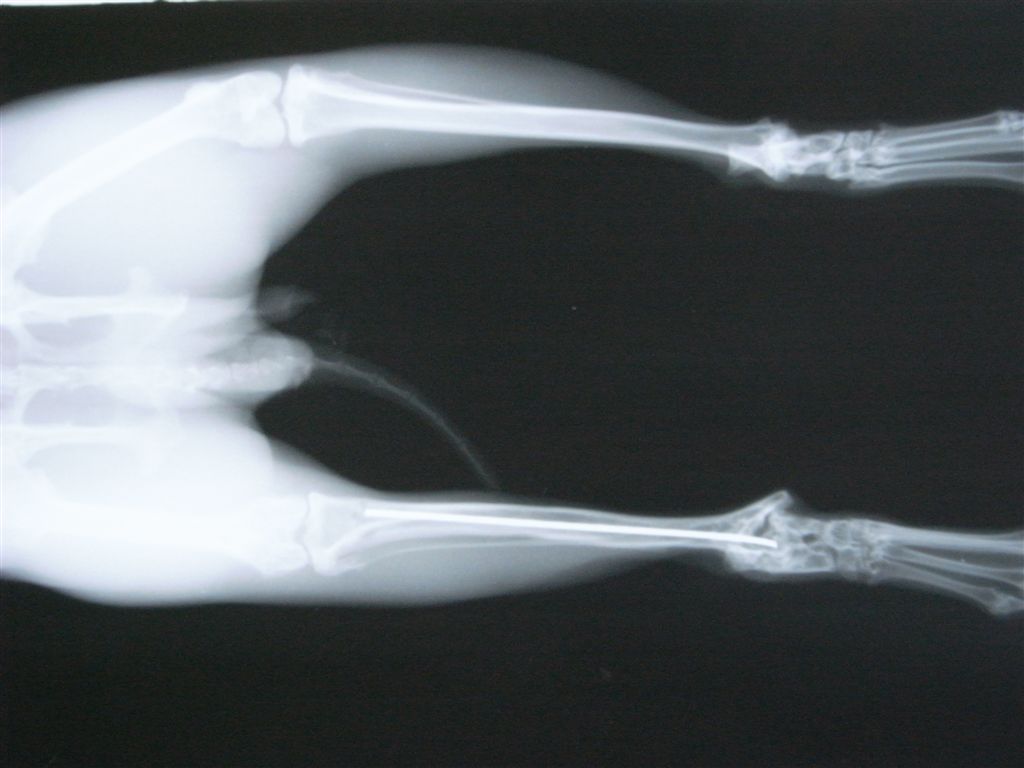

うさぎの骨は簡単に骨折します。俊敏な動きを維持するために、骨が非常に軽く出来ているのですが、そのために強い衝撃を受けるとあっさり折れてしまいます。

骨折する場所は太股の骨(大腿骨)、すねの骨(頸骨)、背骨(脊椎)です。後ろ足の力が強いために起こります。足の骨の場合、骨の中に金属の棒(ピンニング)やプレートで固定をして外側から固定をして、動かないようにケージに入れておきます(ケージレスト)。1ヶ月から2ヶ月ぐらいかかると思ってください。

うさぎ、踵の骨折、骨髄内にピンをいれて固定。

関節に近い骨折だと固定が関節ごと固定するので稼動域が狭くなりやすい。